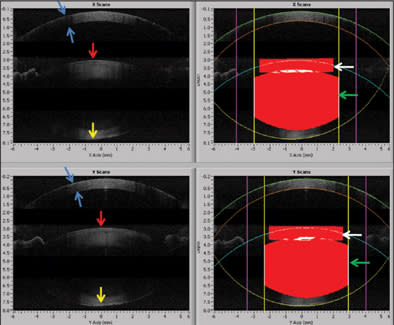

The femtosecond laser enables precise cuts that have important safety and performance implications both peri-operatively and long term. Integrated imaging systems, such as on-board OCT, provide registration to direct the laser both laterally and in depth (Figure 1). For clear corneal incisions, the OCT can provide the corneal thickness at the desired incision location so the architecture for incisions can be properly customized for each patient (Figure 2). This can include the main cataract incision sized for surgical instrumentation, such as the phaco tip and lens injector, and is designed for a watertight seal. It can also include side port incisions. The depth and architecture for relaxing incisions can also be registered, calculated and accurately delivered on the desired axis.

Figure 2. Clear-corneal incision made by the femtosecond laser (red arrows) with perfect tongue and groove apposition of edges of the incision).